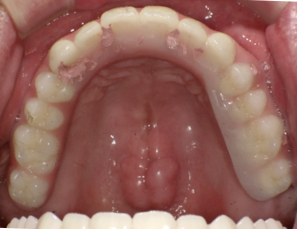

治療前の写真です。前歯がぐらぐらになっています

奥歯がなくなり、前歯ばかりで噛んでいるとフレアーアウトといって前歯がどんどん前に傾いて出てきます。

中途半端に悪い歯を残すと、後々治療が大変になるので思い切ってすべての歯を抜歯します